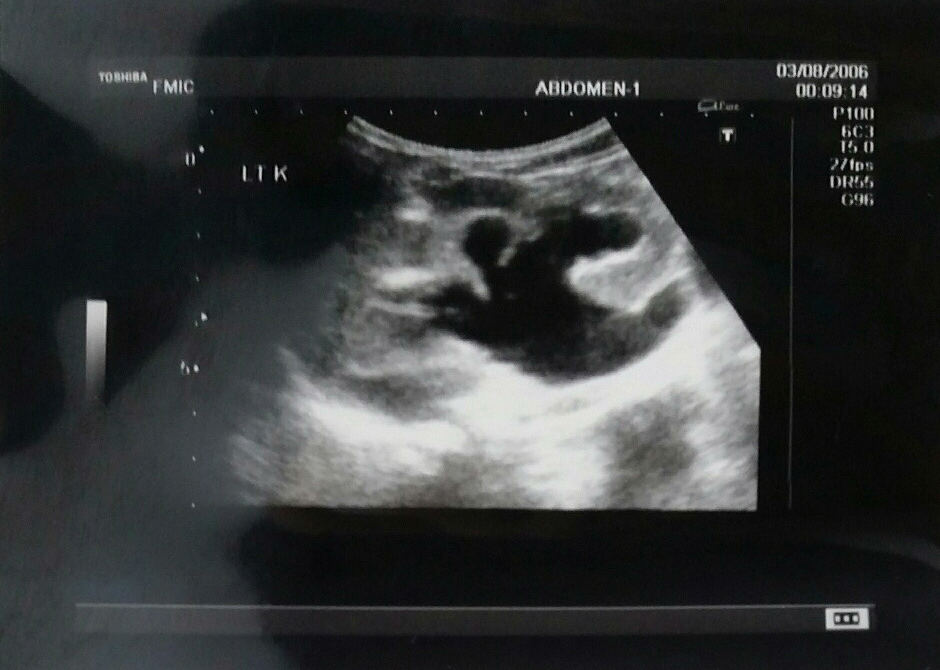

From ultrasoundpaedia.com

Posterior urethral valves ULTRASOUNDPAEDIA Male Posterior Urethral Valve What are posterior urethral valves? What are posterior urethral valves? Posterior urethral valves (puv) are obstructing membranous folds within the lumen of the posterior urethra (figure 1). The valve can obstruct or block the outflow of. Posterior urethral valves (puv) is a condition found only in boys that affects the urethra (the tube which runs from the bladder to the. Male Posterior Urethral Valve.